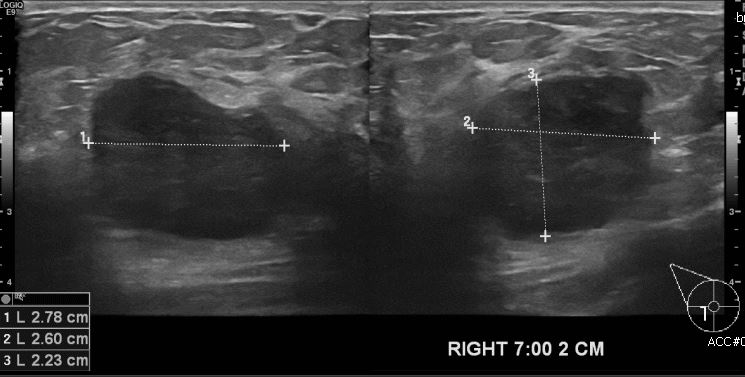

우측 유방에 만져지는 몽우리로 내원하신 40대 여성분으로 우측 유방7시 방향에서 2cm

떨어진 거리의 만져지는 혹 중앙핵생검 시행하여 침윤성 유관암 진단 되었습니다.